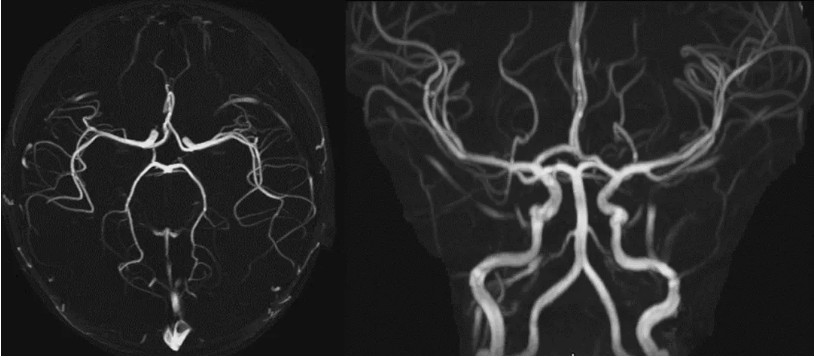

小编已经穷尽洪荒之力,但是并没有找到任何直接或间接证据,导致DWI信号异常。难道是血管畸形? 来个TOF 试试。 TOF MIP重建,未见异常。